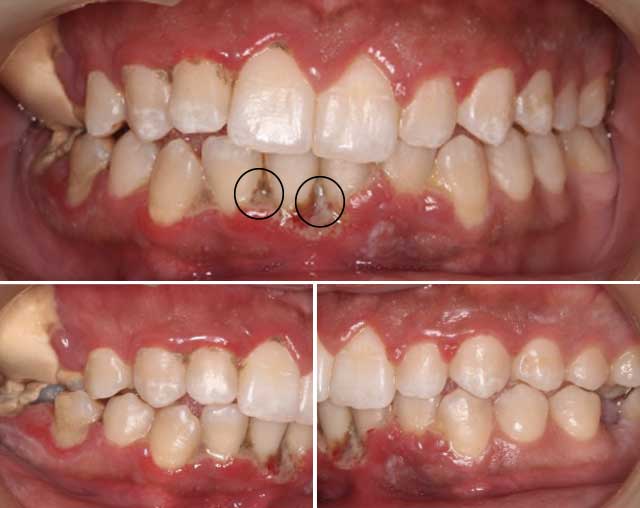

L’examen clinique a révélé une halitose, une nécrose ainsi qu’une ulcération des papilles inter-dentaires recouvertes d’une pseudomembrane. Une papille était absente au niveau du secteur incisif inférieure, avec une accumulation de plaque notée sur la surface des dents. Des dépôts importants de tartre ont été observés au niveau des molaires maxillaires droites ; Cela peut être expliqué par son habitude de mastication unilatérale (Fig 1).

|

Fig 1 : Vues cliniques initiales montrant la nécrose et l'ulcération des papilles inter-dentaires recouvertes d'une pseudomembrane. |